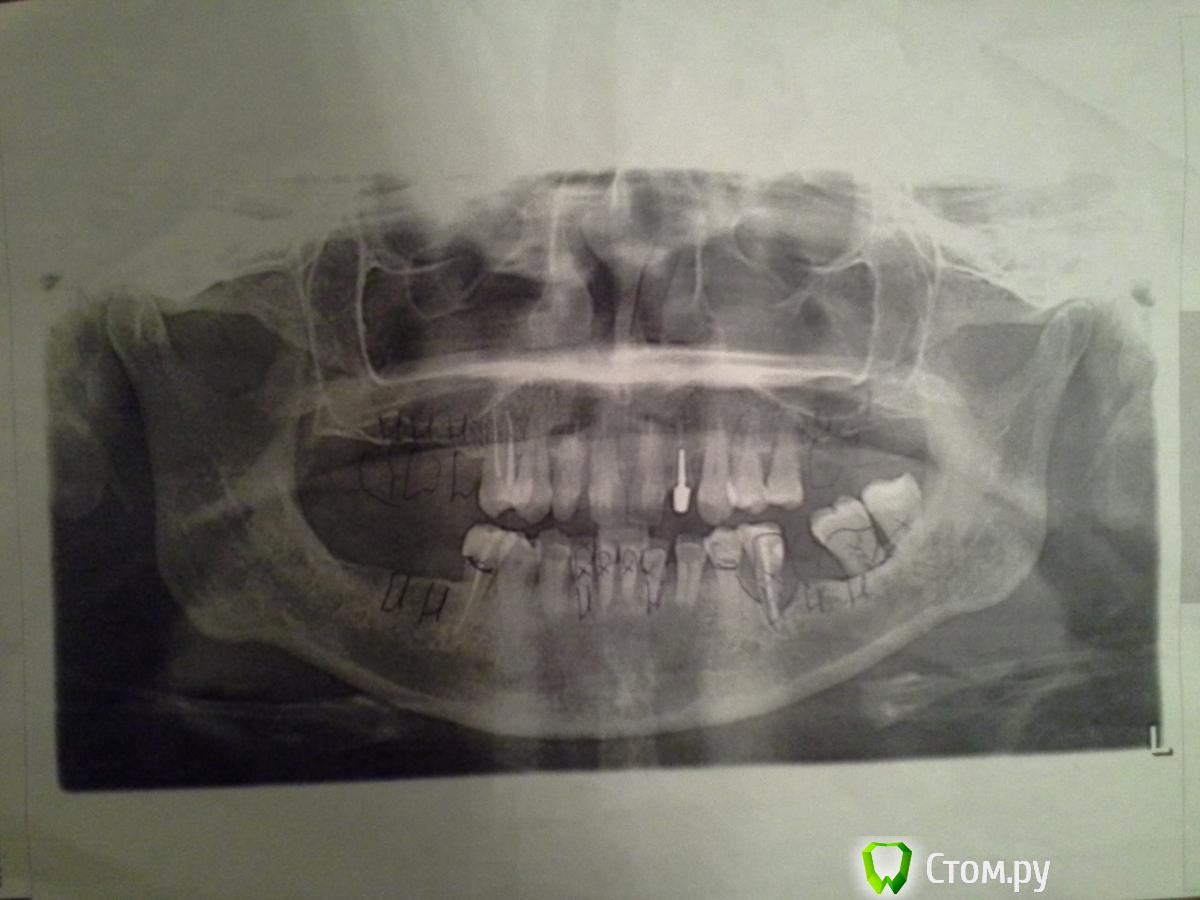

MartyMira Опубликовано 17 января, 2014 Поделиться Опубликовано 17 января, 2014 (изменено) Добрый день, уважаемые специалисты! Важно знать Ваше мнение по имплантации. Сколько имплантатов необходимо в моем случае и возможна ли экспресс (мгновенная) имплантация или базальная (базальтовая) имплантация? Зубы, помеченные крестиками, - удалены. Изменено 17 января, 2014 пользователем MartyMira Ссылка на комментарий

MartyMira Опубликовано 17 января, 2014 Автор Поделиться Опубликовано 17 января, 2014 Еще раз снимок. Ссылка на комментарий

red_butler Опубликовано 17 января, 2014 Поделиться Опубликовано 17 января, 2014 У Вас фото панорамного снимка, напечатанного на простой бумаге, к тому же с рисунками врача. От того что Вы его выложили еще раз, качество лучше не стало. Возьмите снимок в клинике в электронном виде, или сделайте новый. Ссылка на комментарий